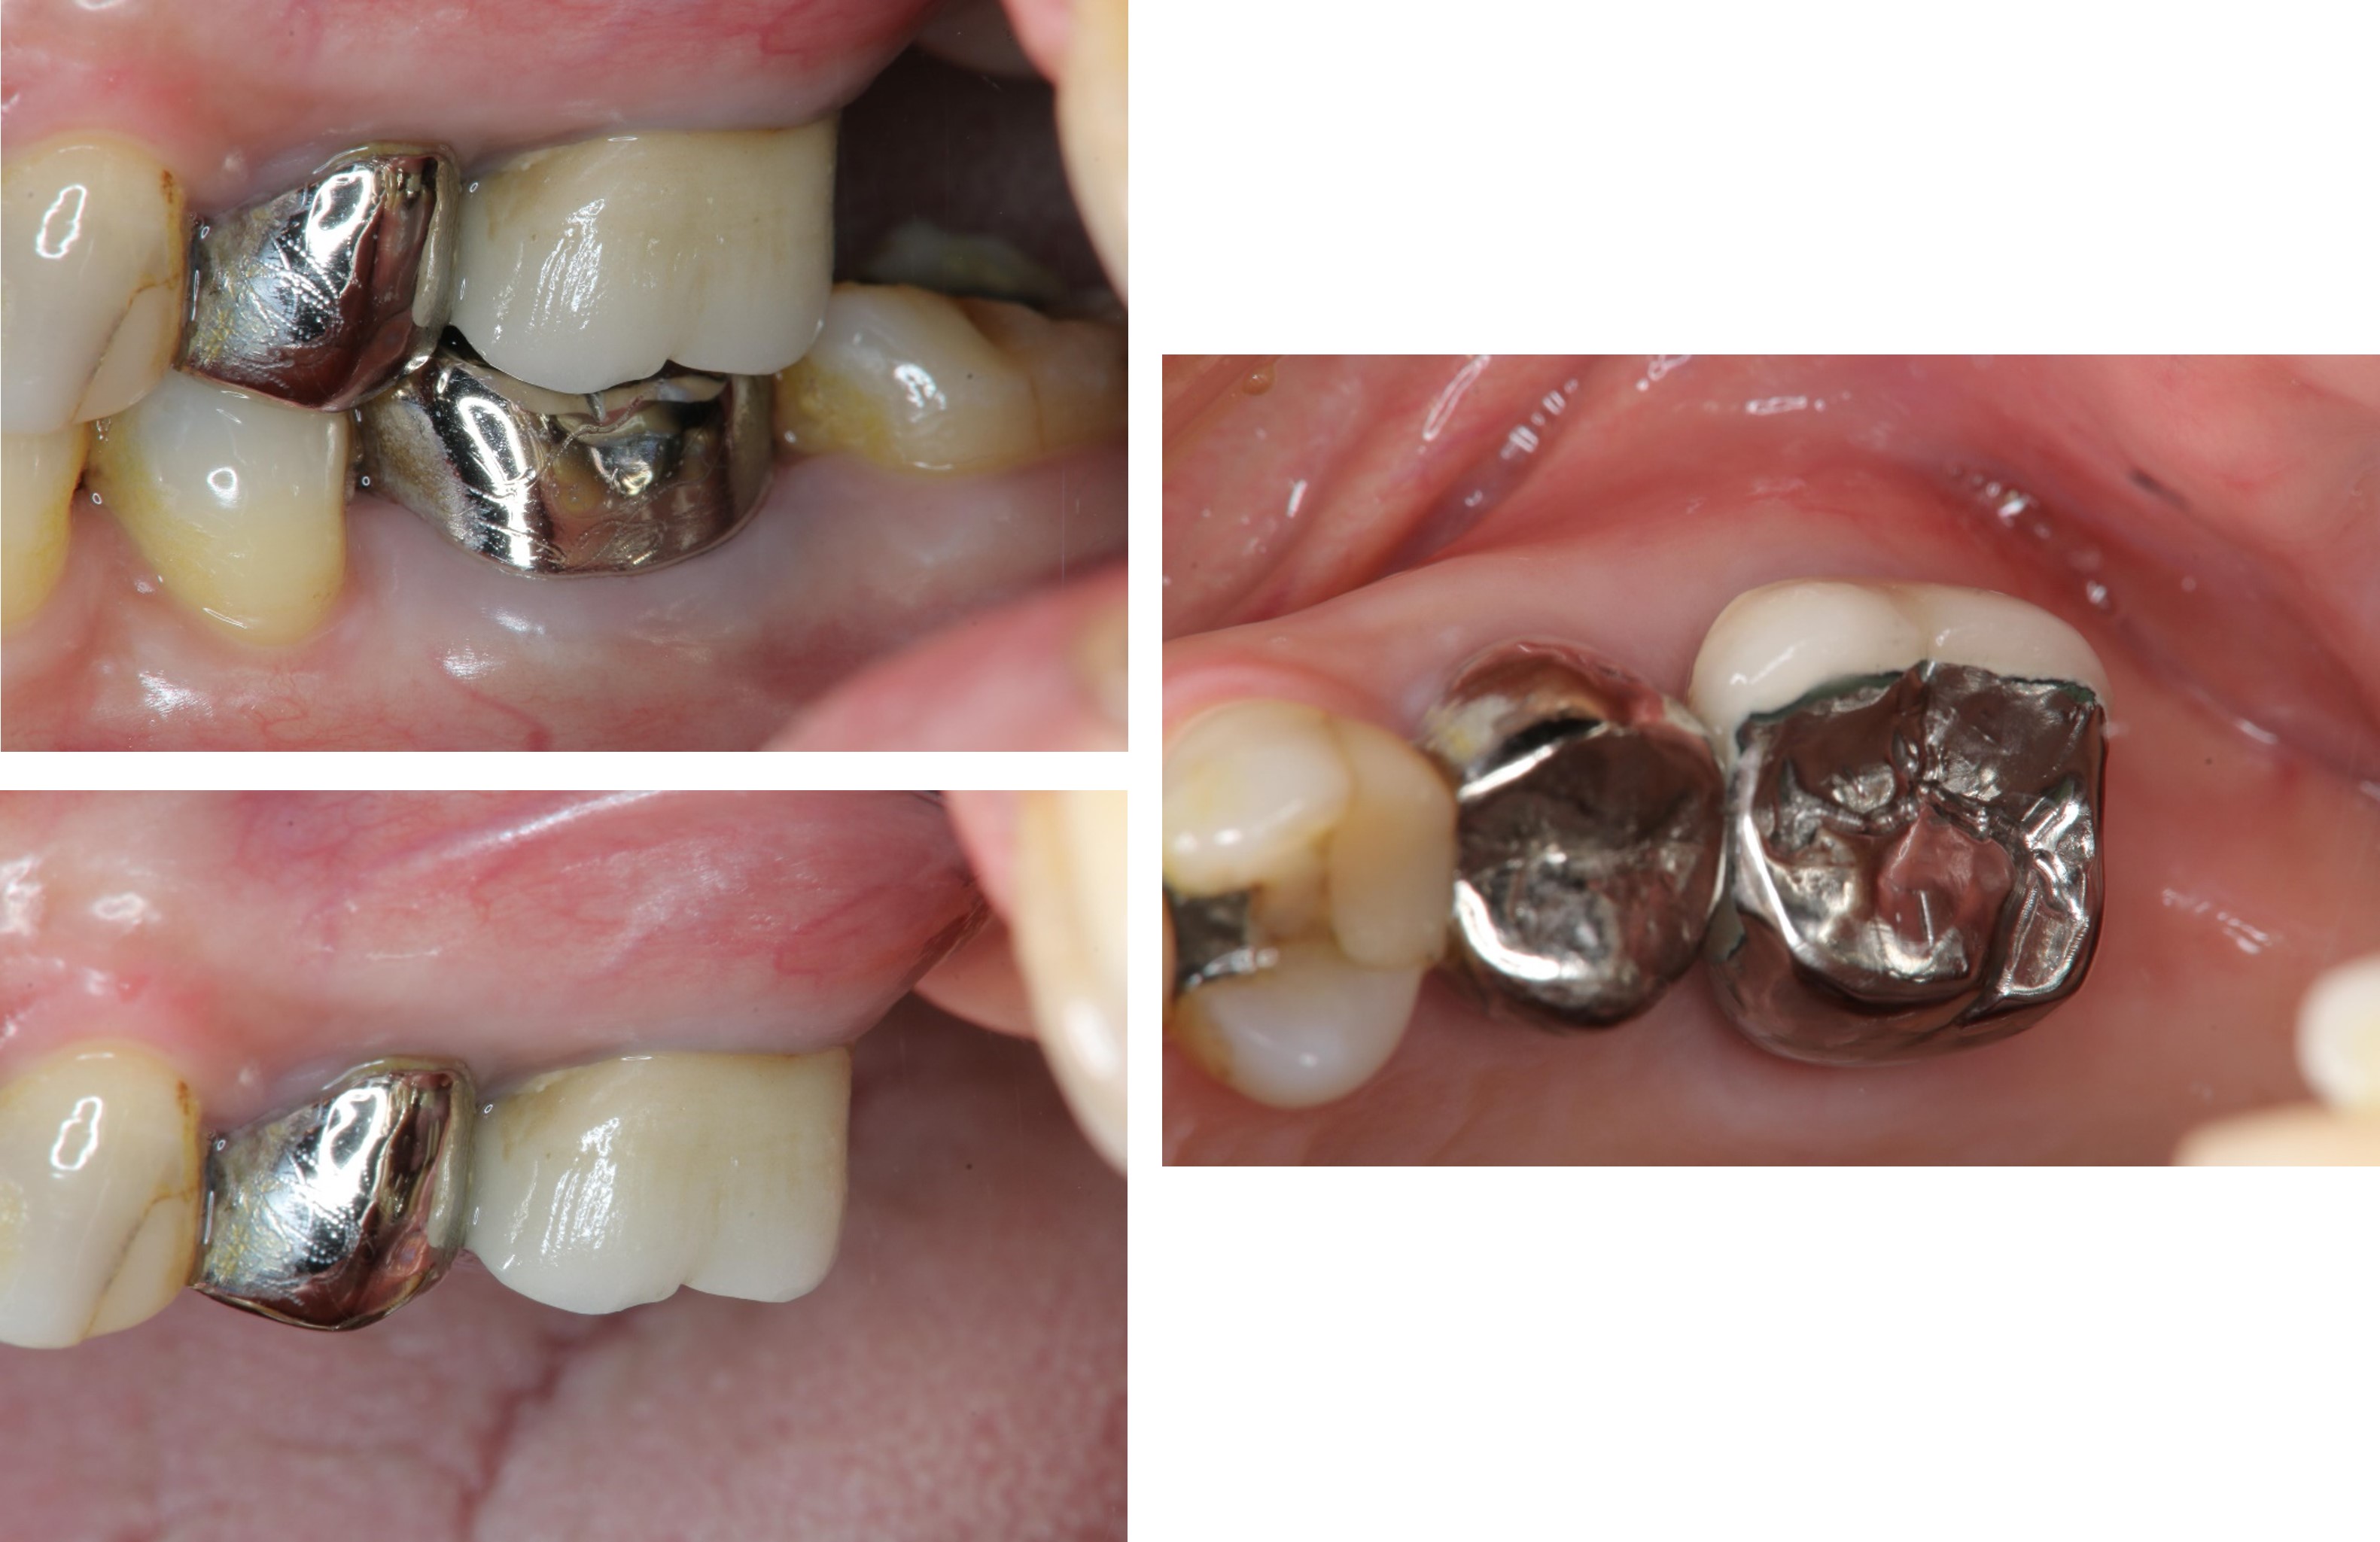

治療後,咬合良好

治療後,密合度良好

術前、術後比較